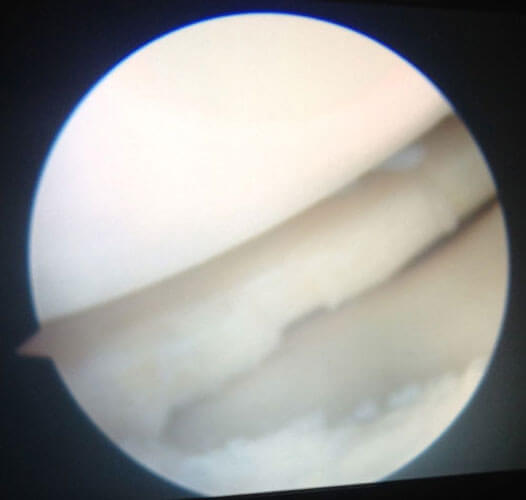

Arthroscopy Surgery